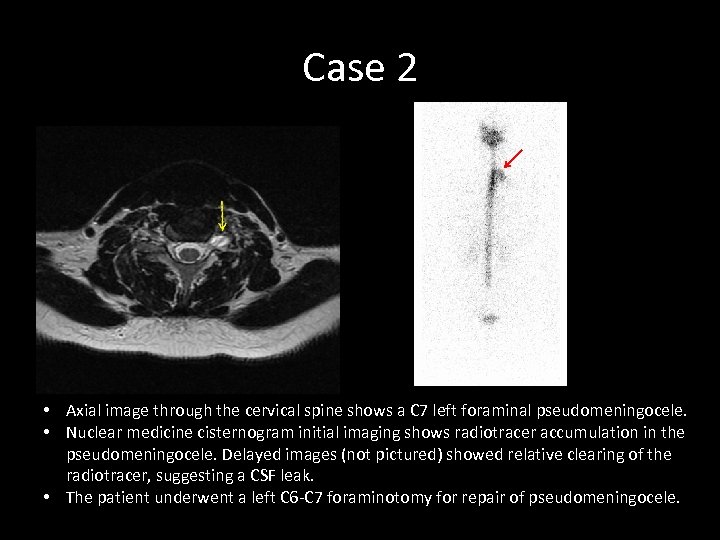

Case 2 • Axial image through the cervical spine shows a C 7 left foraminal pseudomeningocele. • Nuclear medicine cisternogram initial imaging shows radiotracer accumulation in the pseudomeningocele. Delayed images (not pictured) showed relative clearing of the radiotracer, suggesting a CSF leak. • The patient underwent a left C 6 -C 7 foraminotomy for repair of pseudomeningocele.

Case 2 • Axial image through the cervical spine shows a C 7 left foraminal pseudomeningocele. • Nuclear medicine cisternogram initial imaging shows radiotracer accumulation in the pseudomeningocele. Delayed images (not pictured) showed relative clearing of the radiotracer, suggesting a CSF leak. • The patient underwent a left C 6 -C 7 foraminotomy for repair of pseudomeningocele.